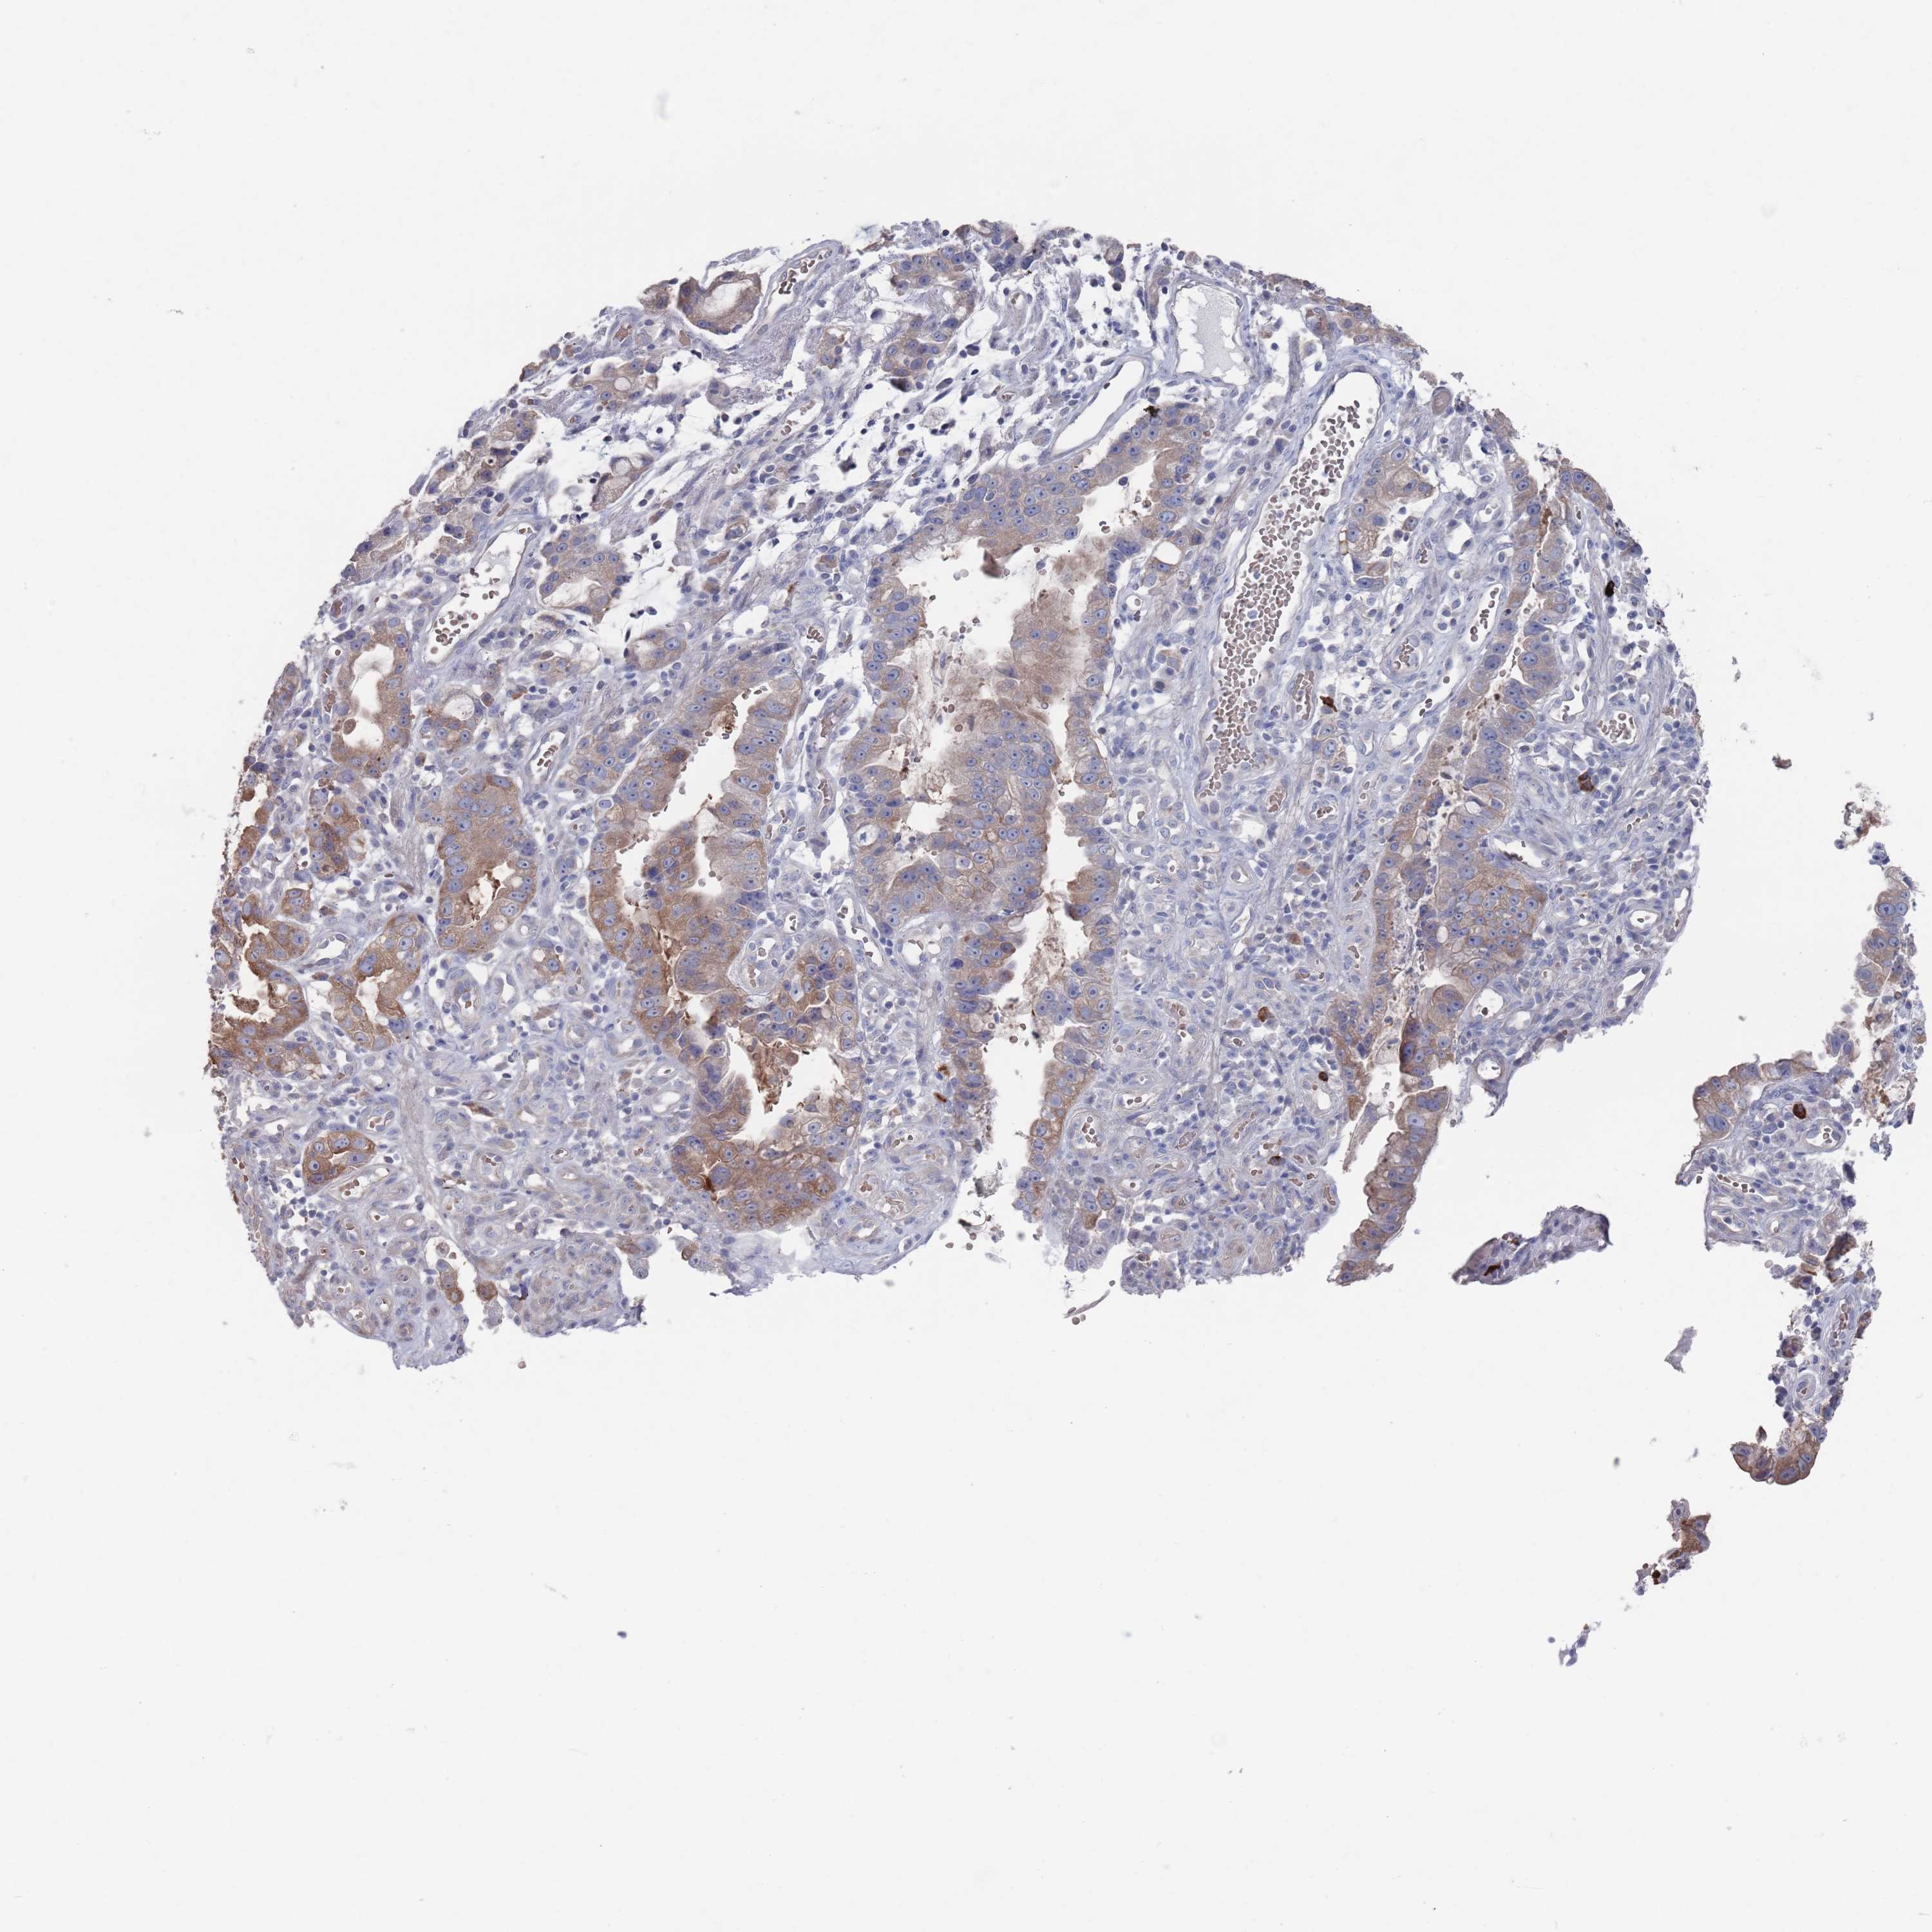

STOMACH CANCER - Protein expressioni

A mouse-over function shows sample information and annotation data. Click on an image to view it in a full screen mode. Samples can be filtered based on level of antibody staining by selecting one or several of the following categories: high, medium, low and not detected. The assay and annotation is described here.

Note that samples used for immunohistochemistry by the Human Protein Atlas do not correspond to samples in the TCGA dataset.

Antibody stainingi

Antibody staining in the annotated cell types in the current human tissue is reported as not detected, low, medium, or high, based on conventional immunohistochemistry profiling in selected tissues. This score is based on the combination of the staining intensity and fraction of stained cells.

Each image is clickable and will lead to virtual microscopy that enables deeper exploration of all samples and also displays staining intensity scores, fraction scores and subcellular localization as well as patient and tissue information for each sample.

Antibody HPA039561

Antibody HPA048126

Staining

High

Medium

Low

Not detected

Intensity

Strong

Moderate

Weak

Negative

Quantity

>75%

75%-25%

<25%

None

Location

Nuclear

Cytoplasmic/membranous

Cytoplasmic/membranous,nuclear

Adenocarcinoma, NOS